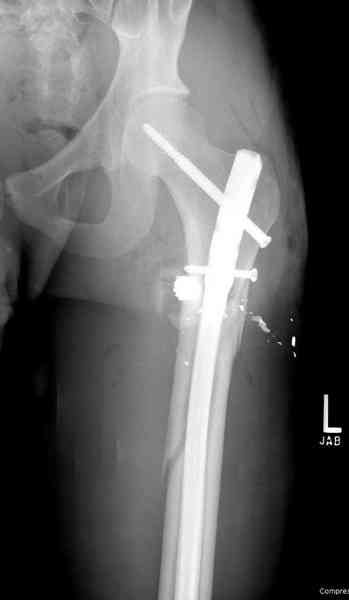

В нашем случае 21 летний боец уличного фронта, фиксацию провели на следующий день, зафиксирован интрамедуллярным штифтом. Не стали делать первичную хирургическую обработку точечной раны, зафиксирован как есть. Клинические снимки:

Вложение не в текстовом формате было извлечено…

Имя     : 3.jpg

Тип     : image/jpeg

Размер  : 37135 байтов

Описание: отсутствует

Url     : http://weborto.net:8080/pipermail/ortho/attachments/20081023/35009bb3/attachment-0011.jpg